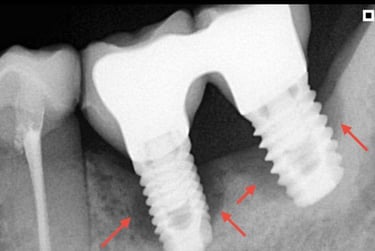

Aspecto Radiográfico Final com Implantes e Coroas

Implante com secreção, sangramento ou partes metálicas expostas?

Isso pode ser peri-implantite, uma inflamação que, quando não tratada a tempo, costuma levar à remoção do implante. A avaliação precoce é fundamental para escolher o melhor tratamento e preservar sua saúde bucal.

Implantes perdidos por peri implantite - Imagens originais — nenhuma contém retoques

Implante feito por outro profissional há cerca de 5 anos desenvolveu inflamação, saída de pus e gengiva inflamada, indicando peri-implantite, uma infecção que pode comprometer o implante se não tratada.